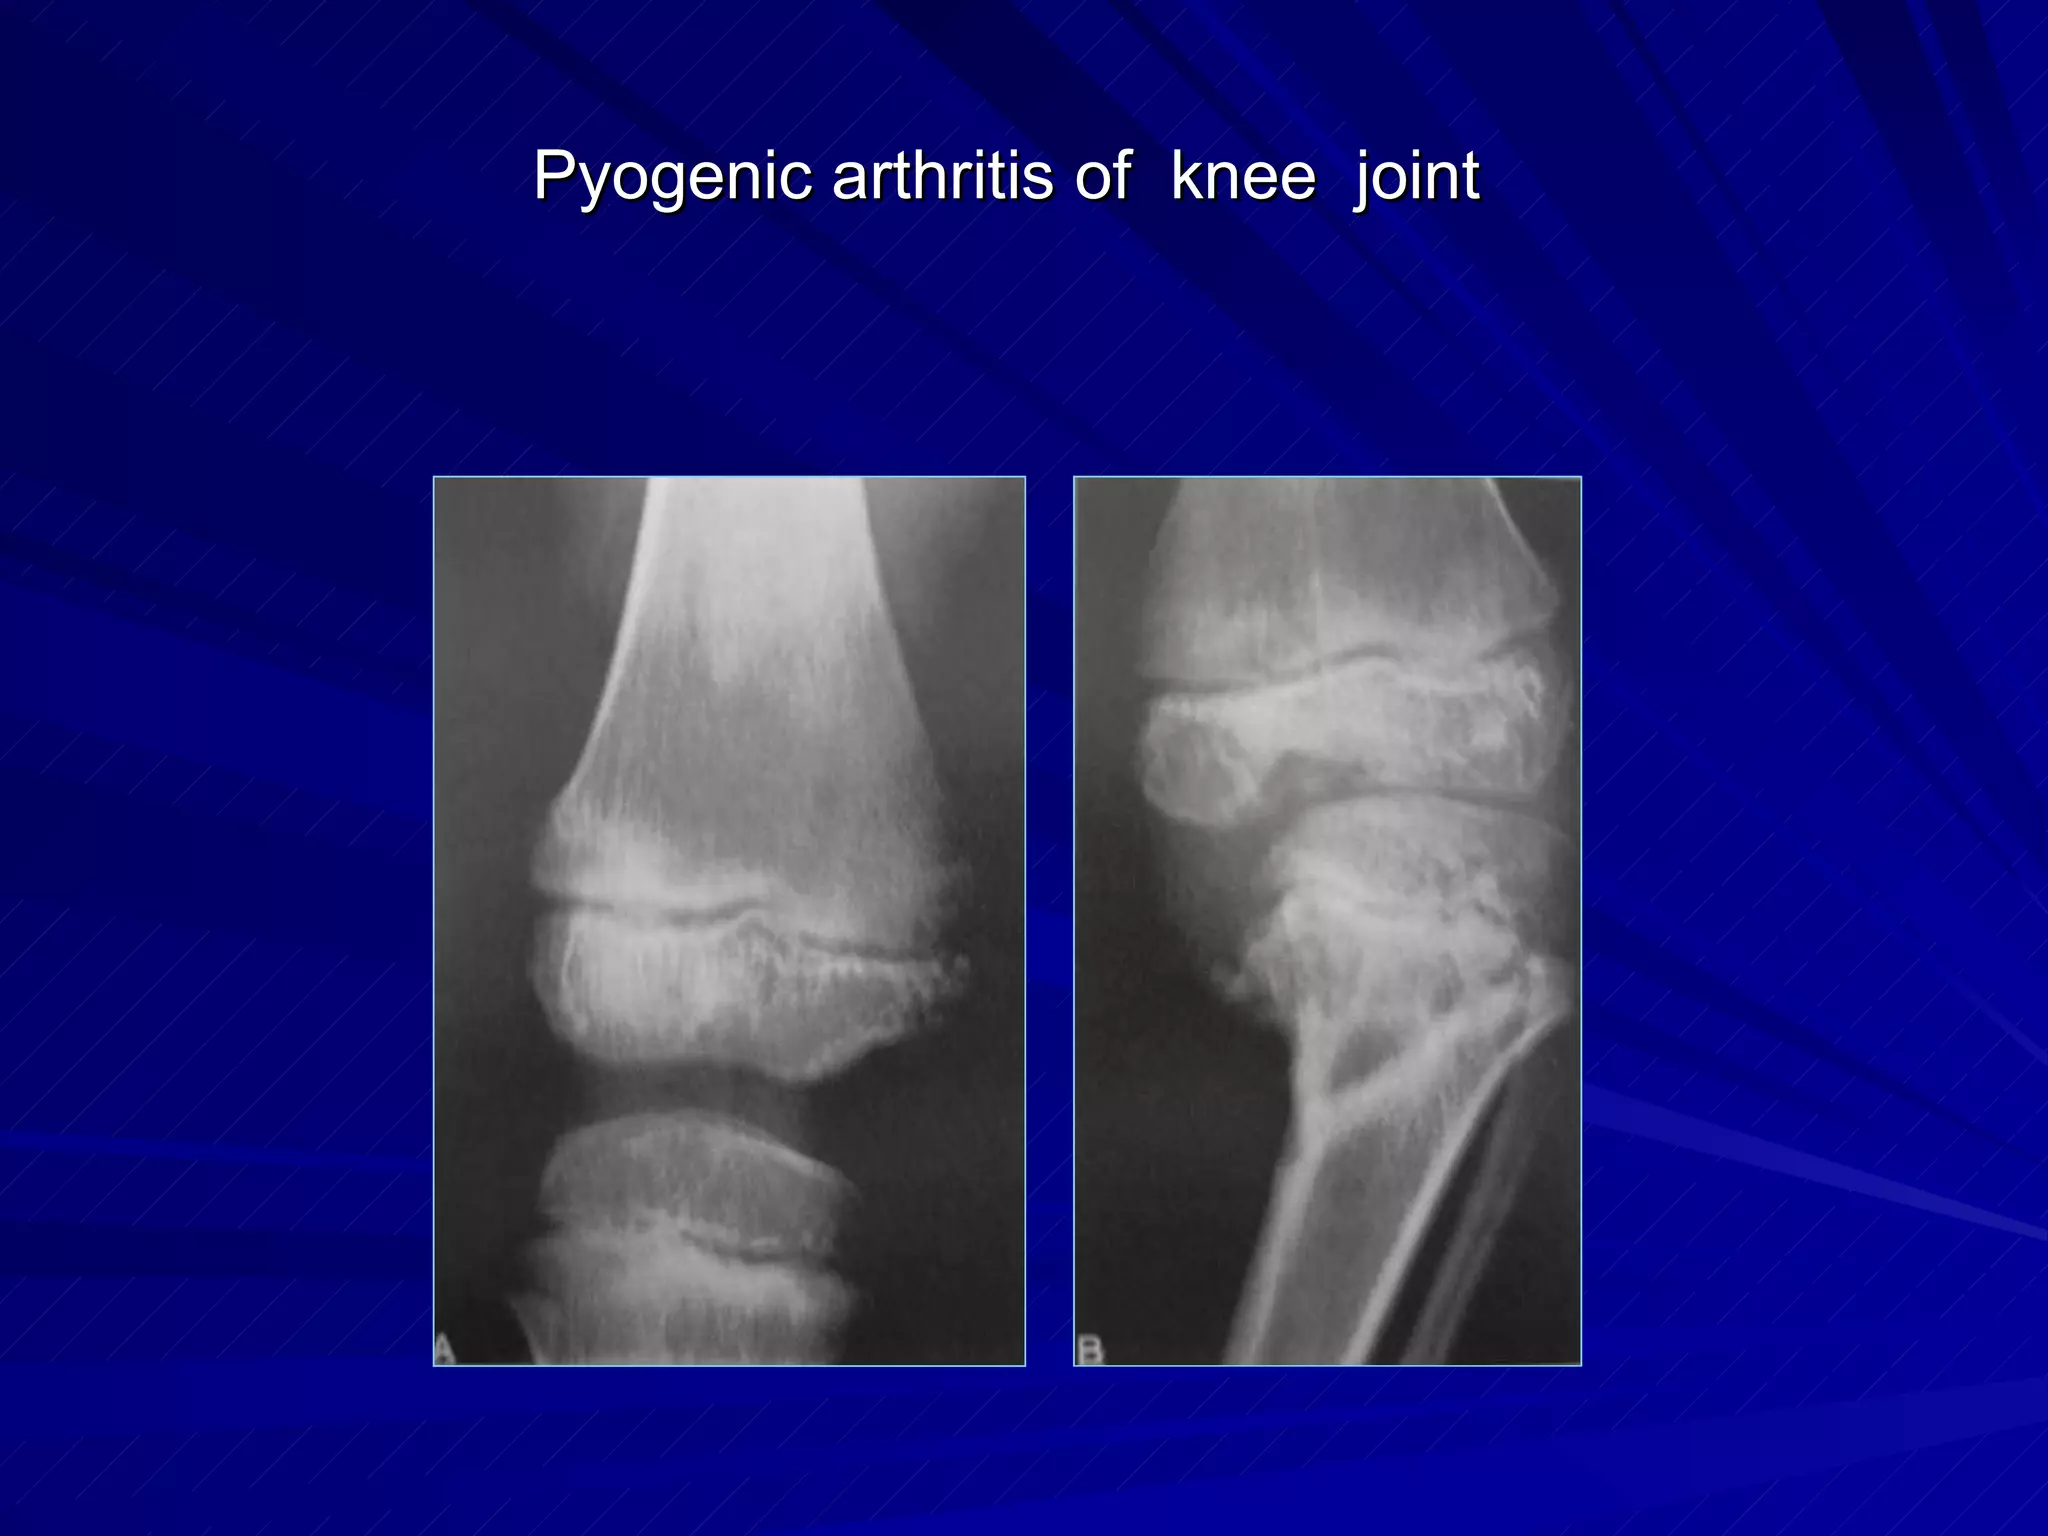

The document discusses various types of infectious diseases of bones and joints, including acute and chronic pyogenic osteomyelitis, Brodie's abscess, tuberculosis of long bones and the spine, and infectious arthritis. Specific examples provided include tuberculosis of the spine, hip, knee, and foot bones as well as pyogenic arthritis affecting the hip and knee joints. The document also mentions normal x-ray appearances of joints and basic features of joint diseases visible on x-rays such as swelling, destruction, degeneration, ankylosis, and dislocations.